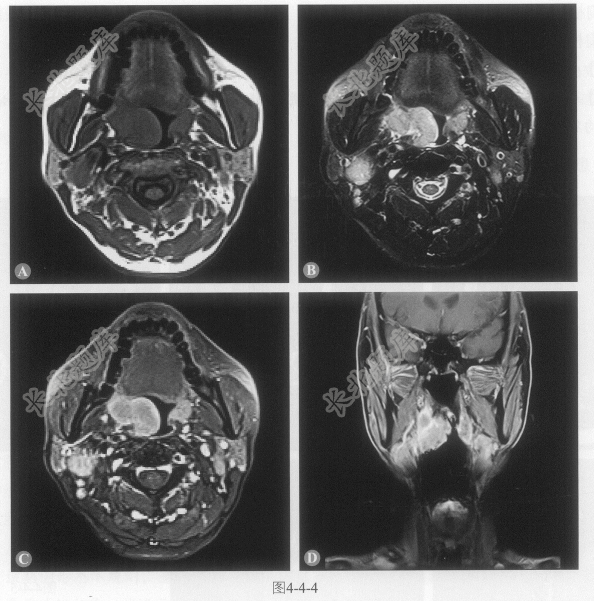

[材料题] 患者男性,65岁,2周前无明显诱因出现吞咽困难,伴咽部疼痛、明显异物感,近2日加重就诊。MRI图像如图4-4-4。

多项选择题1.根据以上MRI图像,下列描述正确的是:

A、双侧颈部可见多发肿大淋巴结

B、病灶信号均匀,边界尚清晰

C、病灶突向喉咽腔

D、口咽右侧壁可见一异常信号肿物影